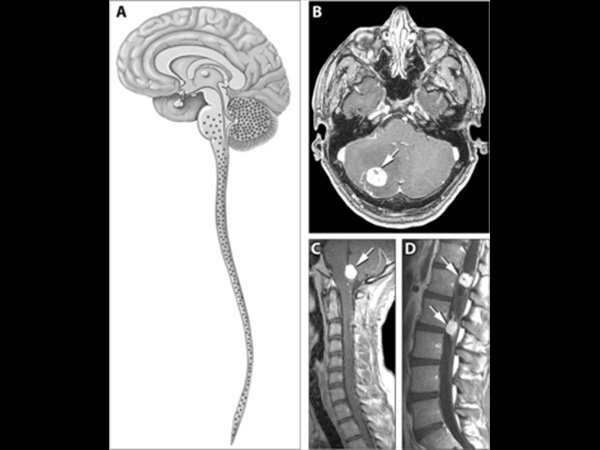

வோன் ஹிப்பல்-லிண்டாவ் நோய் (VHL)

இந்த வகை அரிய நோயால் உடல் முழுவதும் கட்டிகள் வளர்ச்சி பெறும். குறிப்பாக மத்திய நரம்பு மண்டலமான மூளை மற்றும் தண்டுவடத்தில் கட்டிகள் வளர்ச்சி பெறும். அதிலும் இந்த கட்டிகள் இயங்காமல் இருந்தாலும், இதை நீக்காமல் விட்டுவிட்டால், அதனால் பக்கவாதம் அல்லது மாரடைப்பால் மரணத்தை கூட சந்திக்க நேரிடுமாம்.